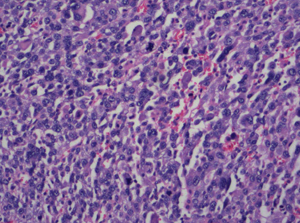

Malignant Melanoma